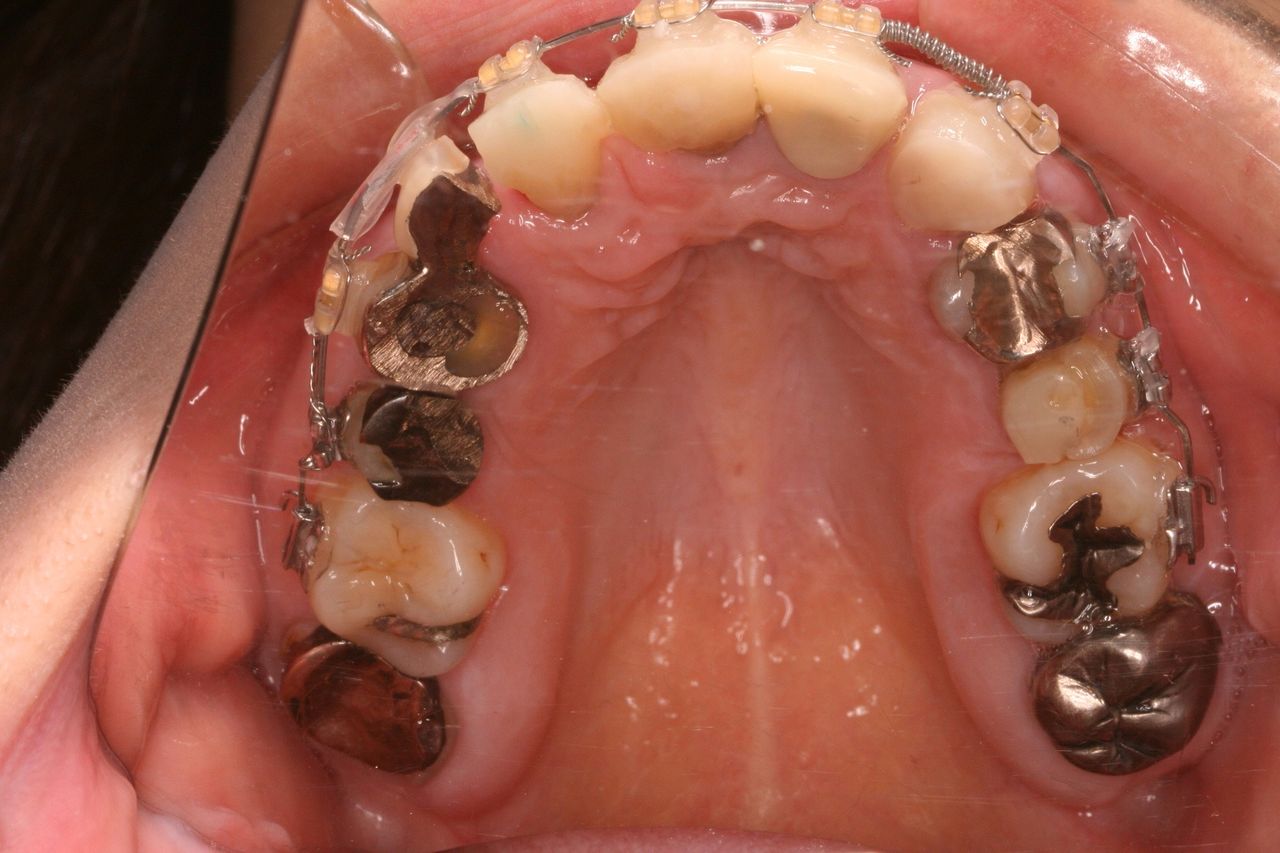

上から見ると、前歯はブリッジとなっており、左右1本づつ歯が欠損しております。

つまり、歯を抜いたのが左右1本ずつで、残りの歯をけずってブリッジにしております。

上からみると向かって左側のみダミーの部分があり、かり歯を入れた右側は仮歯の大きさで隙間をふさいでます。

上からみてもだいぶずれているのがわかります。

上からみてもかなり左右対称な関係になります。